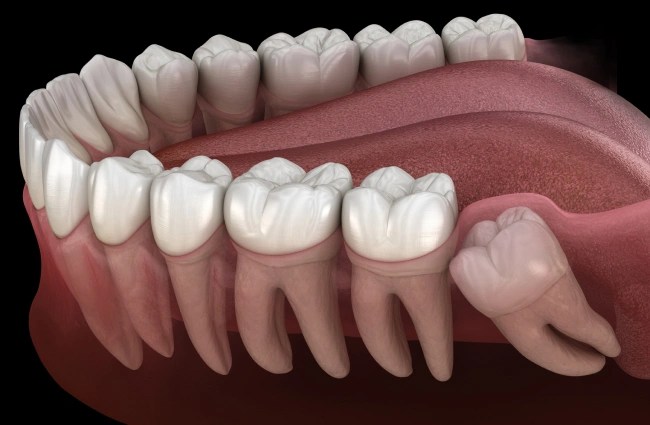

Crowding and Misalignment

Wisdom teeth can exert pressure on neighboring teeth, causing crowding and misalignment. If you notice changes in the alignment of your teeth or have difficulty with your bite, it may be an indication that your wisdom teeth need to be removed.